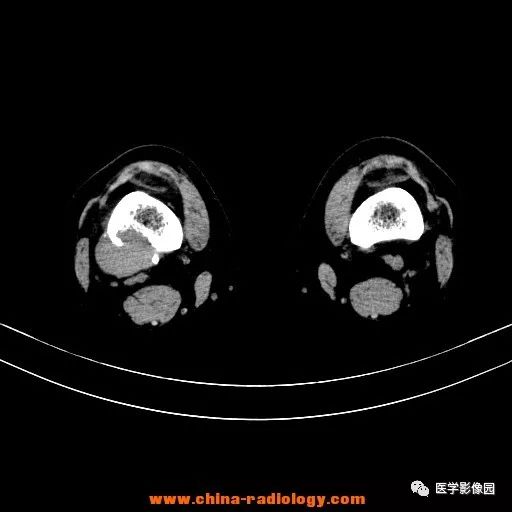

患者女性,29岁,右膝关节痛疼3月余,局部无红肿。

影像学表现:右股骨远端外后方可见局限性骨质破坏及软组织肿块,边界清楚。

病理结果:梭形细胞瘤